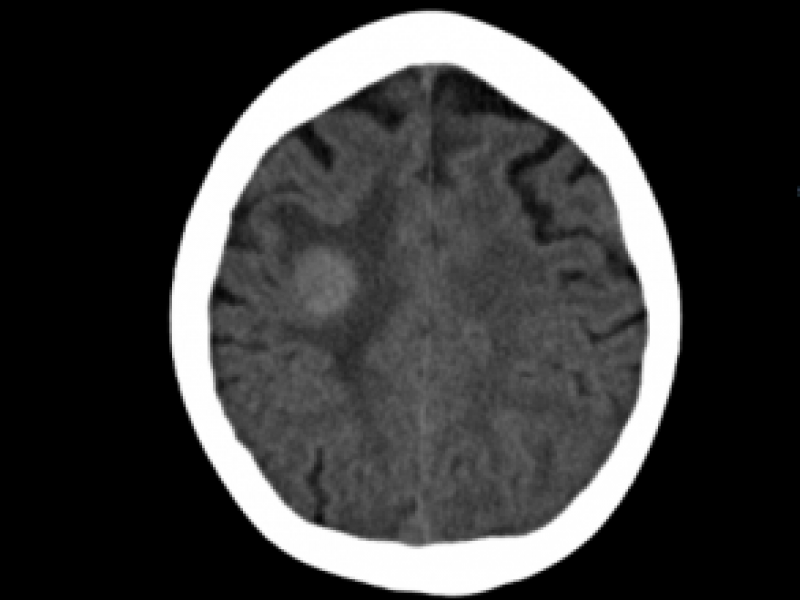

What's the Diagnosis? By Dr. Michael Tom

A 70 yo M w/ a PMHx of HTN and DM presents to the ED with